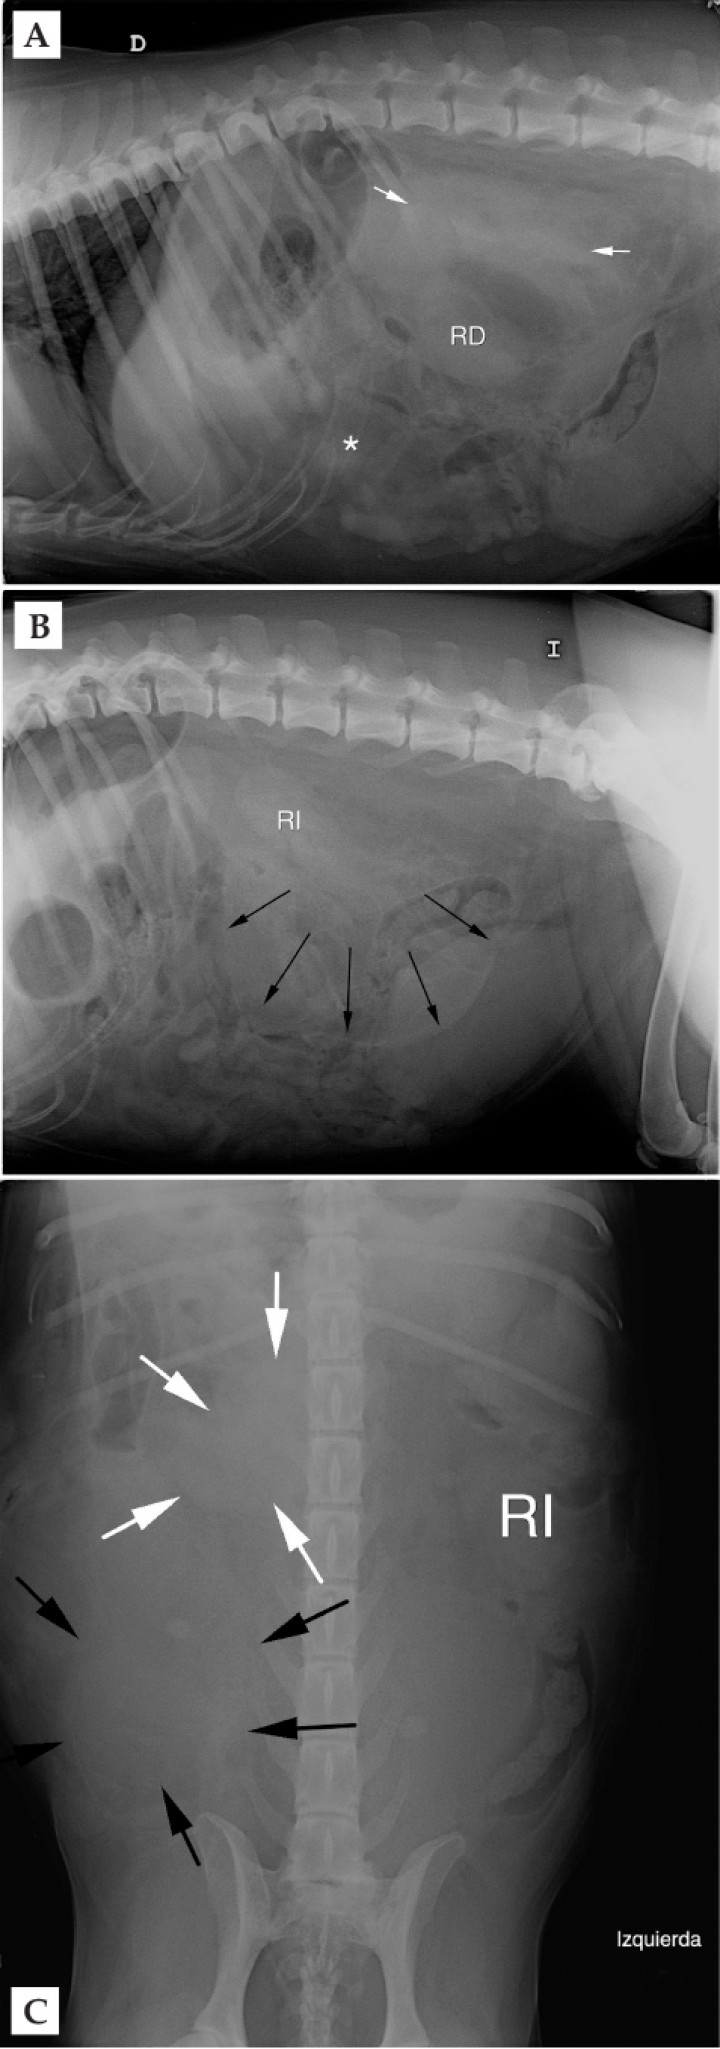

<p>Mismas imágenes que Fig.1. (A) Radiografía lateral derecha: señala posición del riñón derecho (RD), pérdida de definición de serosas a nivel retroperitoneal (entre flechas blancas) y a nivel peritoneal (asterisco blanco). (B) Radiografía lateral izquierda: muestra posición del riñón izquierdo (RI) y efecto masa desde zona retroperitoneal (flechas negras). (C) Radiografía ventrodorsal: señala posición de riñón izquierdo (RI) y masa mal definida localizada en la zona lateral derecha caudal a la última costilla y parcialmente superpuesta con la columna (flechas blancas), así como otra masa mal definida que ocupa gran parte del abdomen derecho caudal (flechas negras).</p>

Mismas imágenes que Fig.1. (A) Radiografía lateral derecha: señala posición del riñón derecho (RD), pérdida de definición de serosas a nivel retroperitoneal (entre flechas blancas) y a nivel peritoneal (asterisco blanco). (B) Radiografía lateral izquierda: muestra posición del riñón izquierdo (RI) y efecto masa desde zona retroperitoneal (flechas negras). (C) Radiografía ventrodorsal: señala posición de riñón izquierdo (RI) y masa mal definida localizada en la zona lateral derecha caudal a la última costilla y parcialmente superpuesta con la columna (flechas blancas), así como otra masa mal definida que ocupa gran parte del abdomen derecho caudal (flechas negras).

<div class=\"frame-2\">Imagen de TC post-contraste reformateada en plano sagital de la región abdominal en ventana de tejido blando (WW400, WL60), donde se muestra masa adrenal (asterisco negro) y hematoma adyacente (x) respecto a riñón derecho (RD) y hemorragia retroperitoneal (asterisco blanco).</div>

Imagen de TC post-contraste reformateada en plano sagital de la región abdominal en ventana de tejido blando (WW400, WL60), donde se muestra masa adrenal (asterisco negro) y hematoma adyacente (x) respecto a riñón derecho (RD) y hemorragia retroperitoneal (asterisco blanco).

Como diagnóstico más probable se considera una neoplasia adrenal, siendo el carcinoma y el feocromocitoma las neoplasias más frecuentes con estos hallazgos. Dicha masa ha formado un hematoma asociado a hemorragia retroperitoneal sin mostrar signos que sugieran la invasión de estructuras adyacentes, pero sin poder descartar la existencia de adherencias.